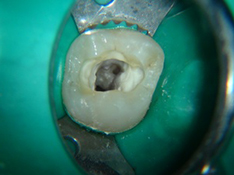

Questo tipo di trattamento consiste quindi nella rimozione della polpa dentaria, nella detersione dei canali radicolari e nella sigillatura con materiale sterile.